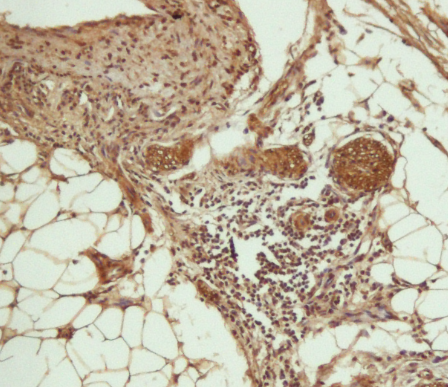

请做过免疫组化的进来鉴定一下我的ICH图片~ 已有5人参与

免疫组化 |